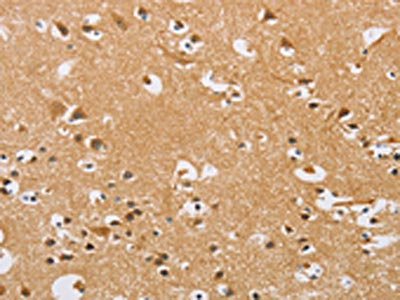

The image on the left is immunohistochemistry of paraffin-embedded Human brain tissue using CSB-PA123263(ARHGEF1 Antibody) at dilution 1/50, on the right is treated with fusion protein. (Original magnification: ×200)